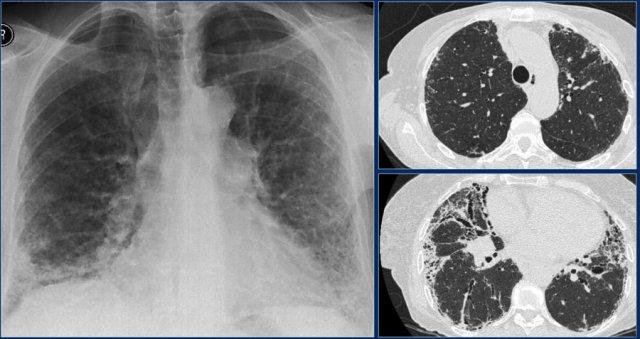

Bệnh mô kẽ

Chẩn đoán phân biệt trên HRCT

Phần lớn kiến thức của chúng ta về các dấu hiệu hình ảnh trong bệnh phổi mô kẽ đến từ HRCT.

Trên HRCT có bốn kiểu hình ảnh: dạng lưới, dạng nốt, tăng tỷ trọng và giảm tỷ trọng (bảng).

Trên phim X-quang ngực thẳng, việc xác định có hay không bệnh phổi mô kẽ và xác định loại kiểu hình ảnh đang gặp phải có thể rất khó khăn.

Trên phim X-quang ngực thẳng, kiểu hình ảnh phổ biến nhất là dạng lưới.

Kiểu hình ảnh kính mờ thường không được phát hiện trên phim X-quang ngực thẳng.

Kiểu hình ảnh dạng nang cũng khó nhận biết trên phim X-quang ngực thẳng.

Khi các nang có thành dày như trong bệnh mô bào Langerhans hoặc tổ ong hóa, chúng thường biểu hiện dưới dạng kiểu lưới trên phim X-quang ngực thẳng.

Tuy nhiên, đôi khi có thể nhận thấy kiểu hình ảnh mô kẽ và trong nhiều trường hợp có thể nghi ngờ UIP dựa trên các dấu hiệu X-quang.

Viêm phổi mô kẽ

Kiểu hình ảnh dạng lưới cấp tính thường gặp nhất do phù mô kẽ trong suy tim.

Nguyên nhân khác là viêm phổi mô kẽ:

- Do virus

- PCP

- Viêm phổi do Mycoplasma.

Bệnh nhân này nhập viện với triệu chứng ho khan và sốt nhẹ.

Đây là nhiễm PCP như là biểu hiện đầu tiên của AIDS.